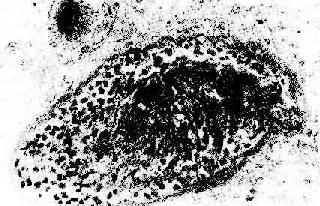

(1)细胞型排斥反应:常发生在移植后几个月,临床上表现为骤然发生的移植肾功能衰竭。镜下可见肾间质明显水肿伴有大量细胞浸润,以单核细胞和淋巴细胞为主,并夹杂一些具有嗜酸性胞浆和水泡状胞核的转化淋巴细胞和浆细胞。免疫组化染色证实有大量CD4+、CD8+细胞存在。肾小球及肾小管周围毛细血管中有大量单核细胞,间质中浸润的淋巴细胞可侵袭肾小管壁,引起局部肾小管坏死(图4-4)。

图4-4 肾移植急性排斥反应

肾间质水肿,肾小管上皮细胞变性,间质及毛细血管内有大量单核细胞